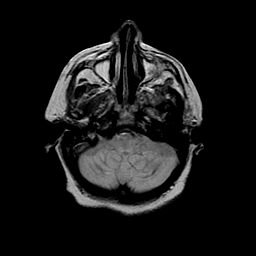

Basal Ganglia Calcification: proton density-weighted MR -- Slice #3

[Home][Help][Clinical] Slice 3